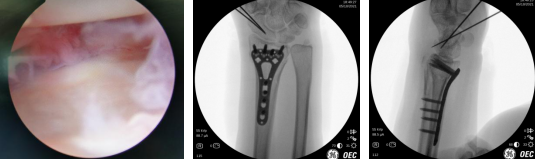

当天,齐伟亚主任手术团队为患者李阿姨进行了“关节镜辅助下左桡骨远端骨折复位内固定术+舟骨骨折复位内固定术”。关节镜辅助下复位桡骨远端骨折端,在左腕掌侧做一1.5公分的切口,放置1块金属接骨板,C臂透视见骨折对位、对线良好,关节镜再次探查,见关节面对位平整,依次对位缝合修复皮下组织。闭合复位左舟骨,术中透视见骨折对位、对线良好,内固定在位。手术顺利。

术中

术后两天,李阿姨恢复良好,顺利出院。术后10个月李阿姨来院复查,手术取出金属接骨板。李阿姨说道:“这10个月,我的生活一点儿都没受影响,手腕怎么活动都不疼,手术第5个月我就和朋友们又打起了网球。”